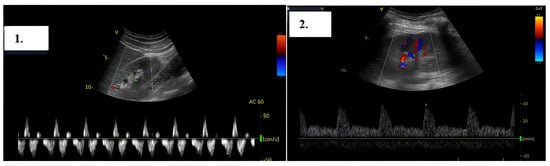

During the hospitalization, the association of severe infection with the myocardium and the saline solution infusion for the antibiotic treatment led to heart failure decompensation with subclinical congestion. The patient was monitored for signs of congestion using systemic ultrasound (inferior vena cava diameter, hepatic veins flow, and renal venous flow) on a weekly basis. Changes in renal venous flow during ultrasound monitoring were suggestive of subclinical congestion. Diuretic therapy with furosemide was initiated with an improvement of/normalized renal venous flow profile, indicative of decongestion (Figure 6).

Figure 6. Right intrarenal-venous flow. In the left image 1, discontinuous intrarenal venous flow with S wave < D wave is observed, while in the right image 2, continuous intrarenal venous flow is seen.